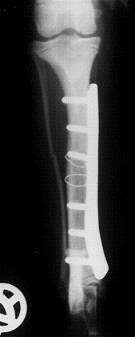

Fallbeispiel:

Unterschenkelfraktur bei einem 6 Monate alten Hundewelpen, Röntgenbild links vor und rechts nach der OP, das Implantat konnte bereits nach 8 Wochen wieder entfernt werden